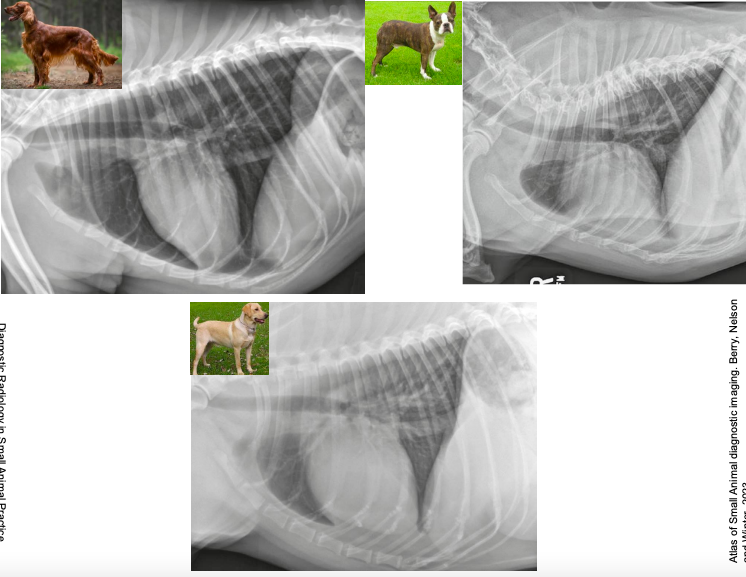

Radiografia laterolateral

Dependiendo de la posición los gases van a un lado o a otro: Decúbito lateral derecho Radiografía Lateral

- Gas en fundus

- Se ve mejor cola del bazo

- Mayor separación de siluetas renales

Decúbito lateral izquierdo

- Gas en píloro

- Mejor visualización delduodeno